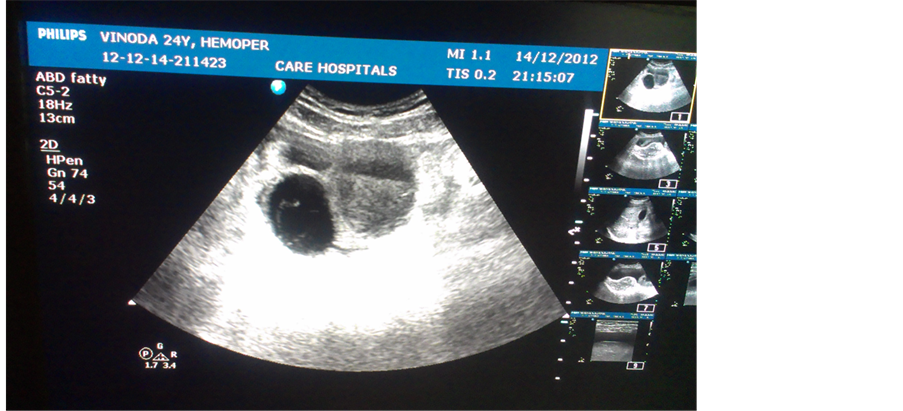

Figure 3. Intra-peritoneal bleeding due to rupture of a cyst in ovary.

Three of the 7 complications occurred during the study period. Two cases had major intraperitoneal bleeding. One was due to rupture of corpus luteal cyst of ovary, she was found to have severe anaemia. She was given 2 PRBC transfusions and anticoagulants were stopped for 3 days. IV antibiotic coverage was given.Evaluated with serial daily ultrasound for monitoring of regression of intraperitoneal haemorrhage (Figure 3). And other case was due to rupture of haemorrhagic cyst of ovary. Both cases were noted to have increased INR. There was no menstrual complaint in both the cases. Both were treated by conservative measures.